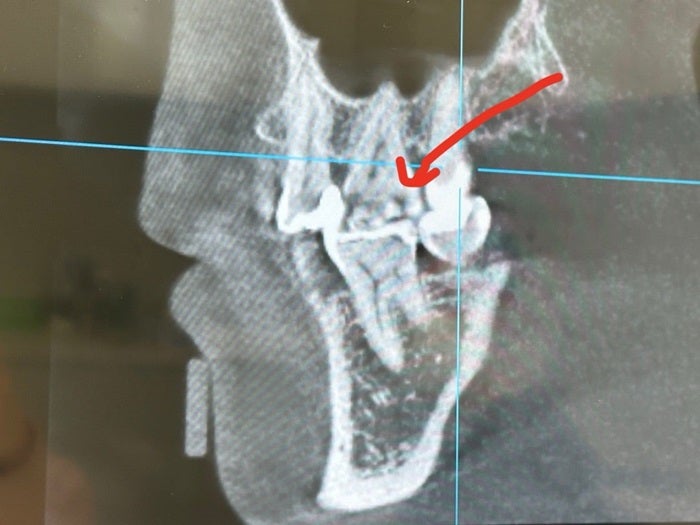

続けて「外見から見てもわからないから、レントゲンの力、すごいよ。この陰が出来てるところが虫歯なんだってさ」とレントゲン写真を公開し「痛くも痒くもなかったからさ、衝撃」とコメント。「昔、詰め物をして、その隙間から食べかすが入っちゃったみたいだ。それで、歯の奥の方が虫歯」と原因について説明し「詰め物の隙間から侵入しちゃうのって…どうしようもなくない…?!笑」とつづった。